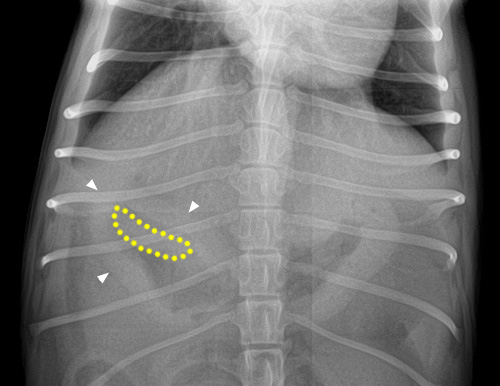

Pas évident ce corps étranger ! Il y a sur la projection latérale une structure très opaque (minérale à métallique) dans le pylore mais cette dernière n’est pas visible sur la projection VD. Pourtant , il y a bien quelque chose dans le pylore sur la VD mais qui semble plus large et d’opacité de tissus mous.

Étant donné que le chien démontrait toujours des signes d’obstruction intestinale, il est allé en laparotomie afin de retirer ce mystérieux corps étranger. On voit sur les radiographies post-op que le corps étranger a bien été retiré.

Et qu’est-ce que c’était ? Un autocollant «puffy» avec un endos métallisé.

Les différences d’opacité relative du corps étranger étaient vraisemblablement liées à son orientation par rapport au faisceau principal, i.e. plus opaque lorsque la tranche était exposée (à cause de la feuille métallisée je présume) et moins opaque de face. Un peu le même principe que les vaisseaux pulmonaires dans le parenchyme.